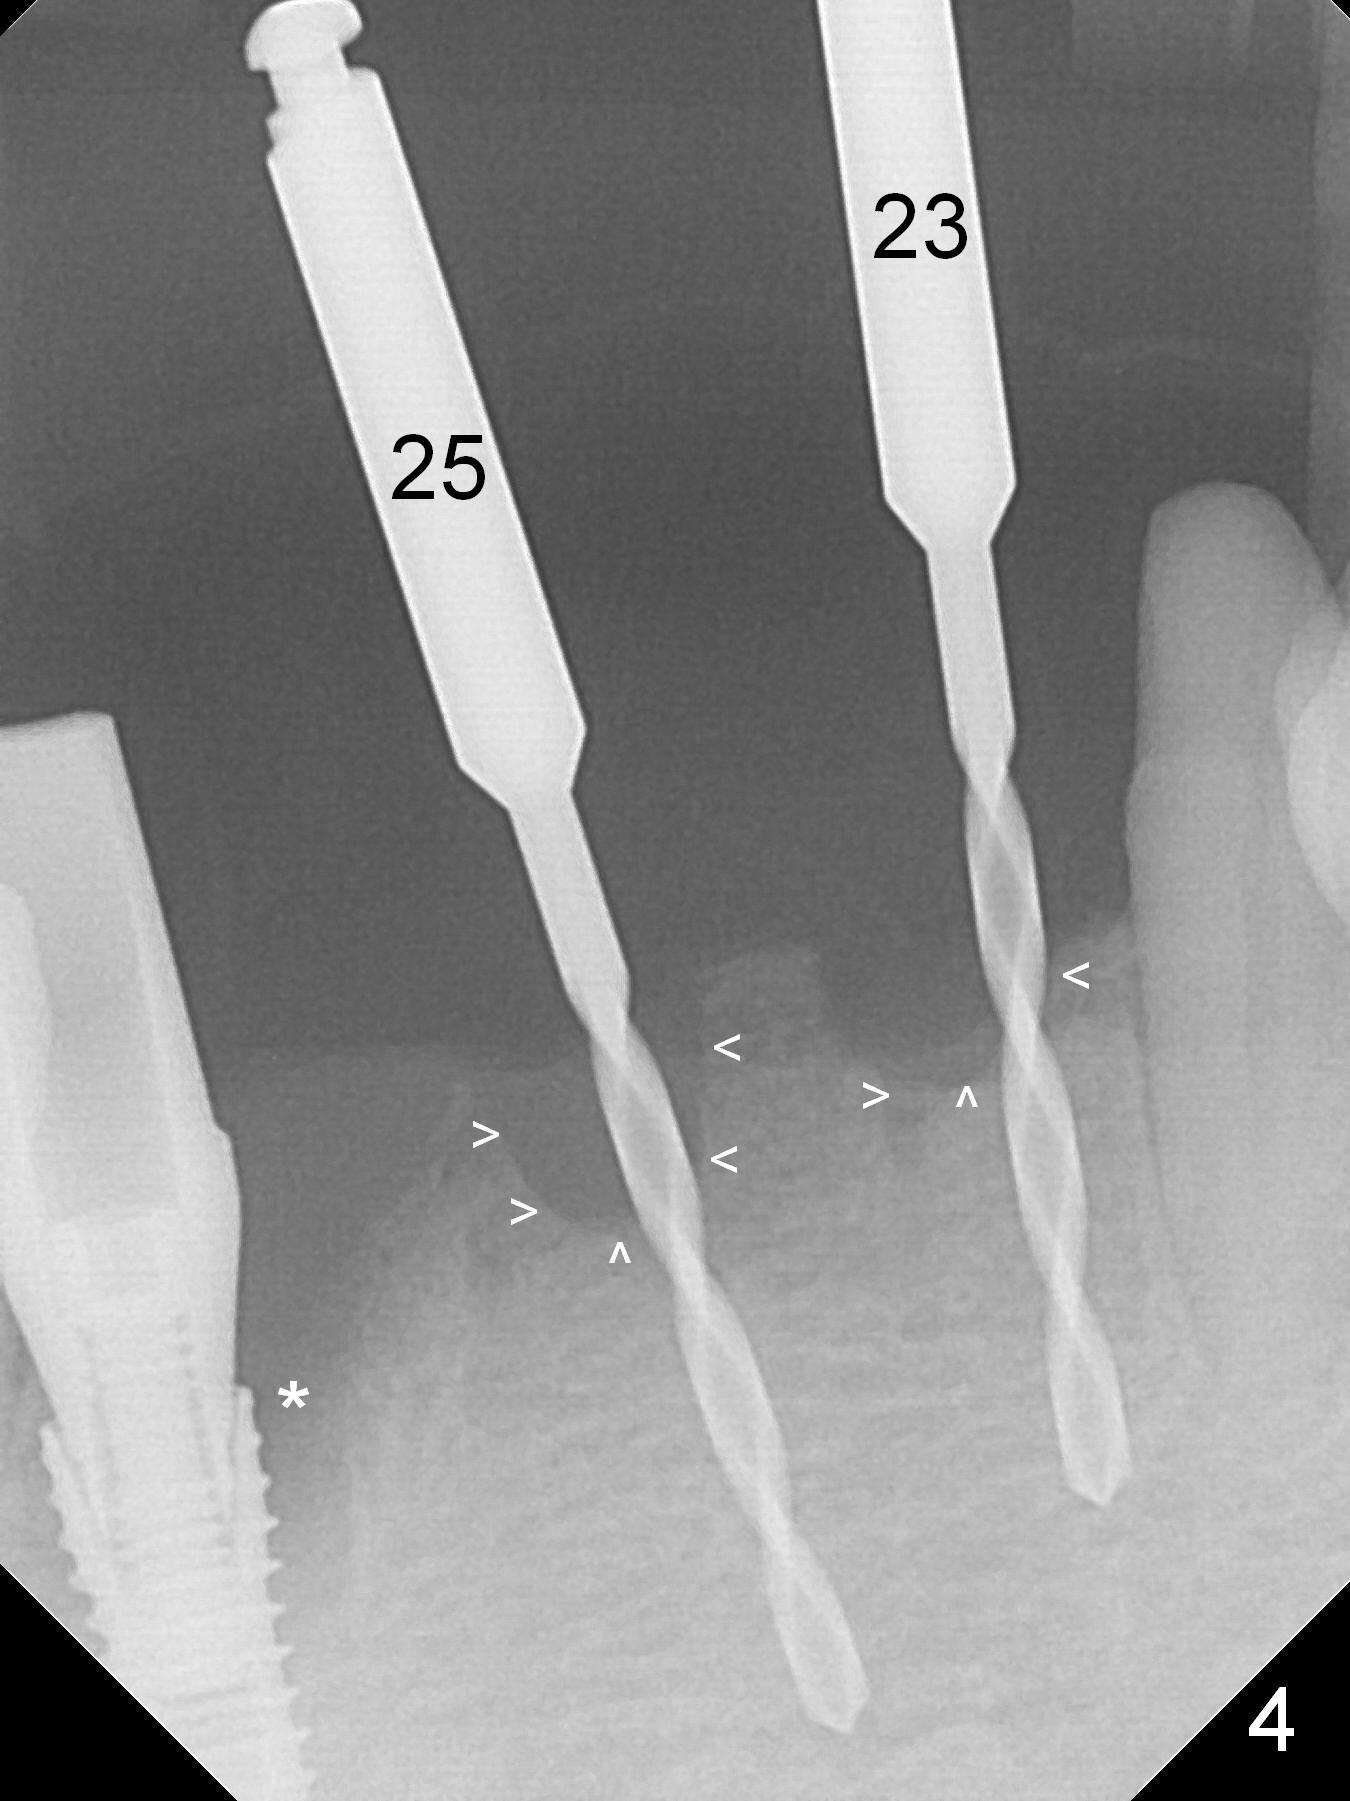

There is severe buccal gingival recession at #27 (Fig.1 arrow), as compared to that at #22. After removing the bridge and extraction of #27 (Fig.2 with severe loss of the buccal plate), a 3x18 mm drill is used to finish osteotomy (Fig.3). A 3.8x13 mm UF implant (Fig.3 green line) will be placed with 9 mm in the apparently solid, native (new) bone (blue line), while the coronal 5 mm will be occupied by the 5 mm cuff of a cemented abutment (pink line). The white dashed line is the gingival margin. The osteotomy is initiated as lingual as possible so that there will be at least 2 mm buccal gap when the narrow implant is placed. In spite of effort and precaution (guided surgery could control the trajetory), the coronal end of the implant tilts buccally so that a 4.5 mm 15 ° A 4 mm angled abutment is placed slightly subgingival (except buccal; Fig.5 A).

Since the ridge between the lower canines is atrophic (Fig.2), osteotomy starts at #23 and 25 after crestal reduction (Fig.4 arrowheads), Two of 2.5x12(4) mm 1-piece implants are placed (Fig.6). The implants at #23, 25 and 27 and the tooth #22 support an immediate provisional bridge (Fig.7).